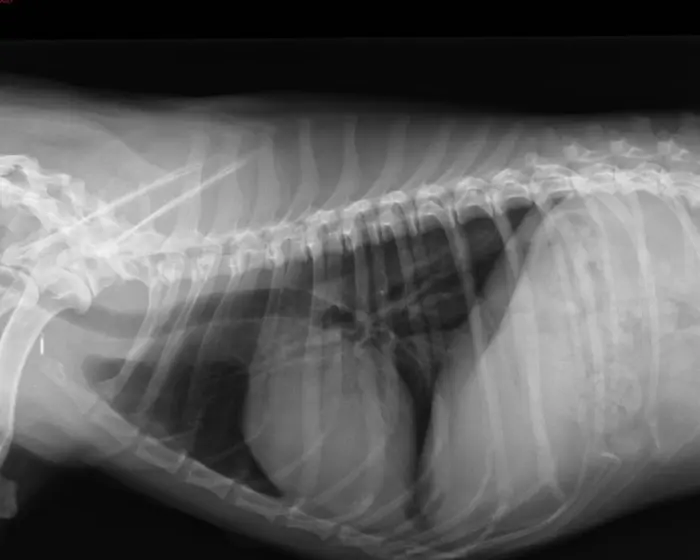

Røntgenundersøgelse af luftvejene

Hvis patienten viser tegn på en luftvejssygdom, har vi ved røntgenundersøgelsen mulighed for at vurdere om det skyldes:

• Lungebetændelse

• Væske i lungerne

• Lungekræft

• Sammenklappet luftrør

• For lang gane

• Brok i mellemgulvet